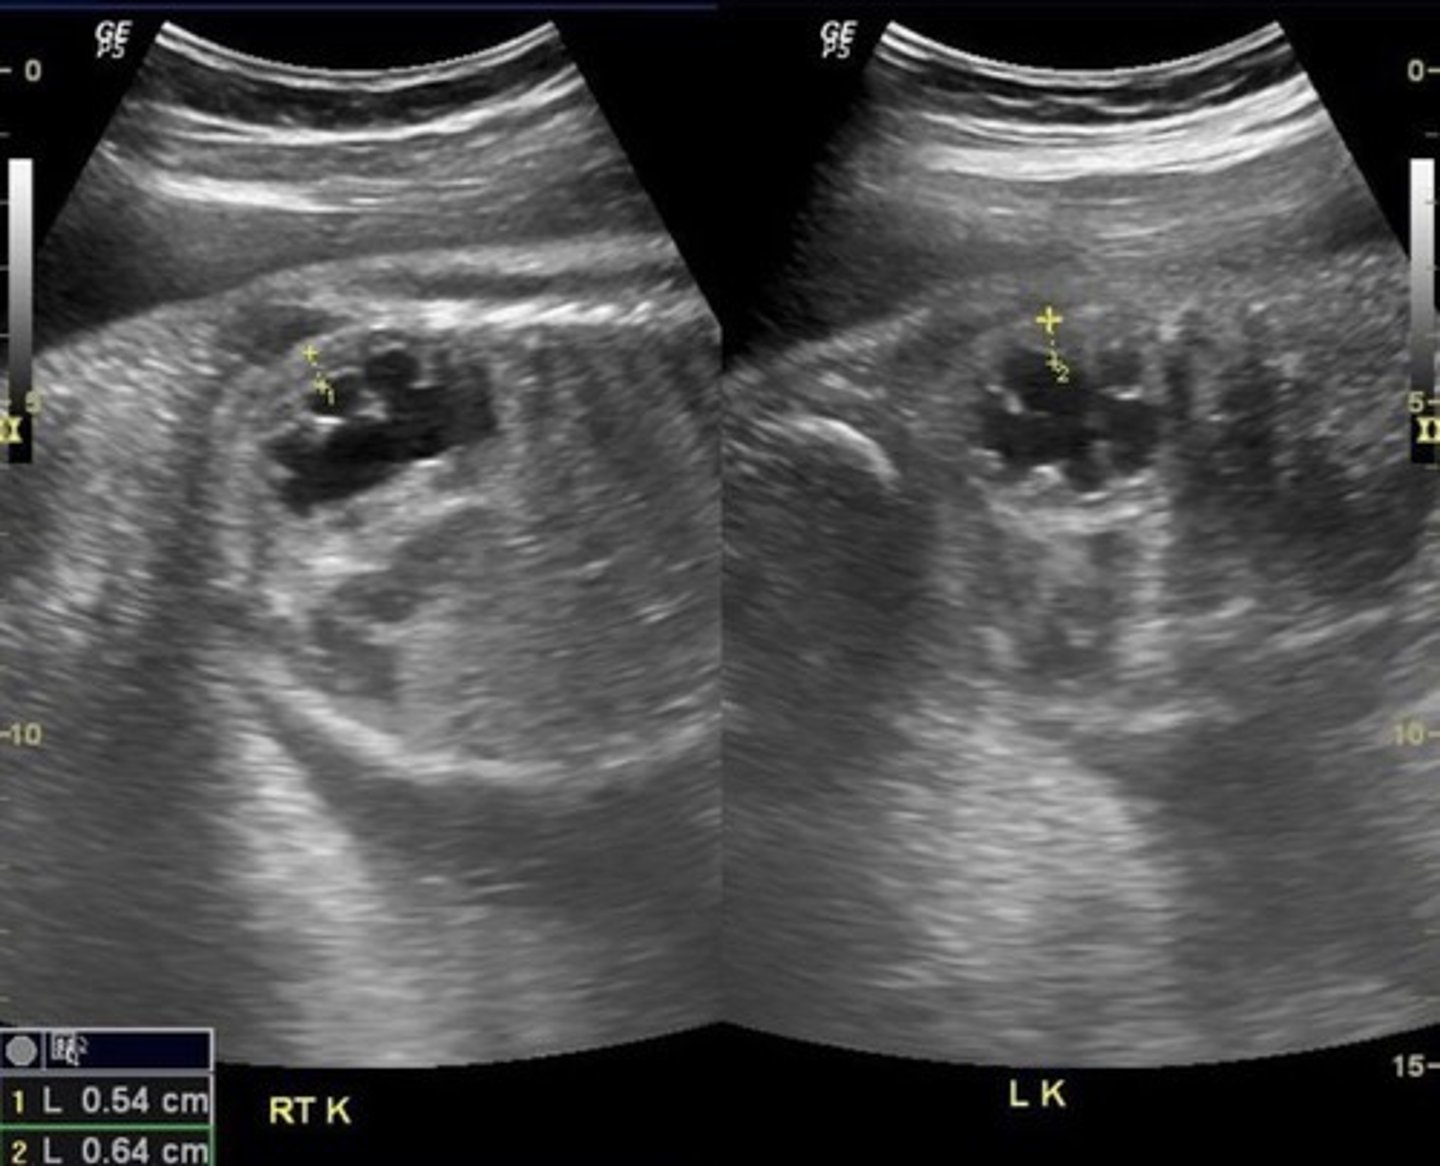

Grade 4 Hydronephrosis

Pelvis is > 10 mm

Marked dilation of calyces

Mild thinning of cortex

Grade 5 Hydronephrosis

Severe thinning of cortex